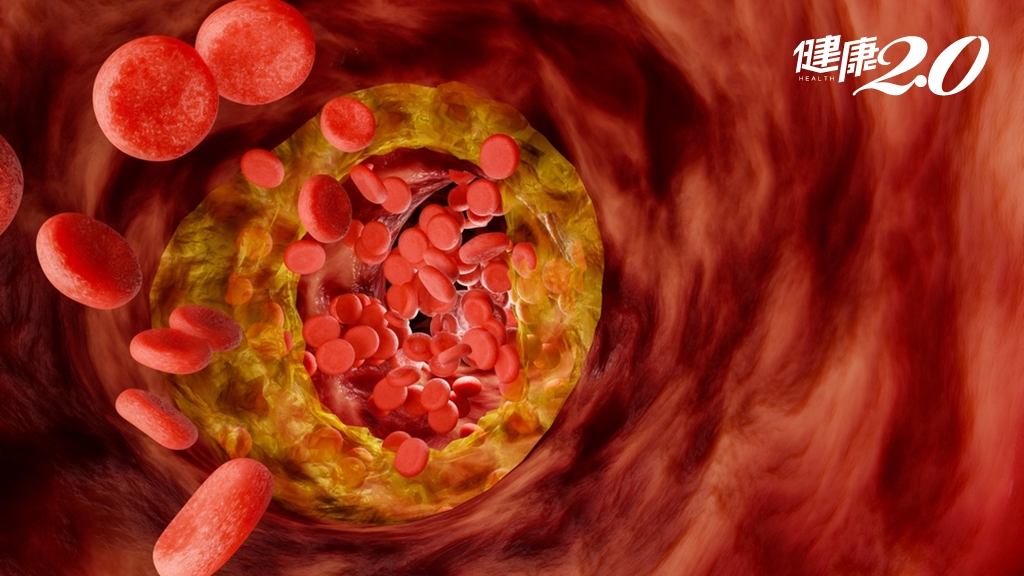

大豆蛋白含植酸、乳清蛋白代謝含氮廢物加重腎負擔

以現在崇尚減脂增肌者喜歡補充的大豆蛋白和乳清蛋白來說,大豆蛋白含抗營養因子如植酸,可能影響營養素吸收並加重消化器官負擔。乳清蛋白代謝後會產生較多含氮廢物,需經腎臟過濾,過量攝取會增加腎臟負擔,尤其對腎功能不佳者,更可能損及腎臟健康。

巫宏傑說,如果腎功能受損,不只不能隨意增加蛋白質攝取量,第三期慢性腎臟病患因腎功能大幅下降,應開始限制蛋白質攝取,優先選擇高生物價值蛋白質如雞蛋、魚肉和瘦肉,以攝取必需胺基酸。同時須確保足夠熱量維持代謝,避免分解肌肉供能而產生更多含氮廢物,加重腎臟負擔。